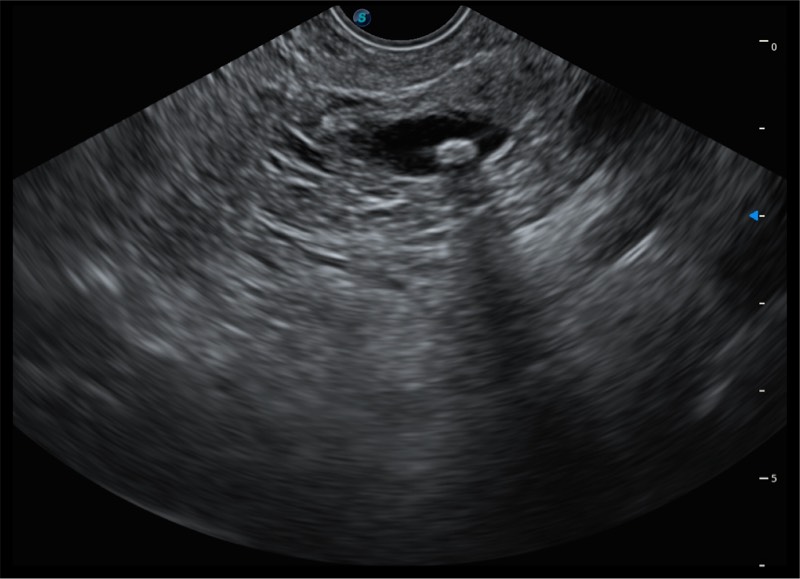

基于二十年的超声技术积累,百老汇电子游戏官网提供了最新一代的独立超声主机,在提供高质量图像的同时满足多学科使用。具备常见多普勒技术并提供弹性成像、声学造影等高端影像技术。新一代传感器具有更强的抗干扰能力并减少图像伪影。

4.0mm大钳道

12.6mm先端部外径

150°超声扫描角度

4-12MHZ宽频输出